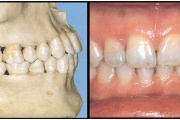

Normaalse jäävhammaskonna pilt küljelt ja eest vaadatuna.